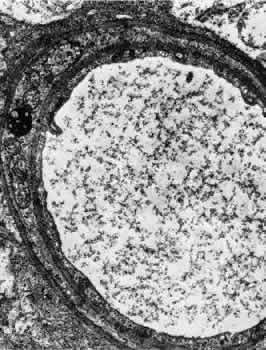

Retinal Arteries and Arterioles The retinal arteries are branches of the superior and inferior papillary arteries. Each papillary artery typically divides again on the surface of the optic disc to form temporal and nasal branches. The anatomical division of the retinal arteries into superior and inferior halves is usually maintained throughout the retina because vessels normally rarely cross the horizontal raphe. The major branch arteries are about 120 μm in diameter and course within the nerve fiber layer and ganglion cell layer of the retina. They are smaller in diameter and straighter in course than their accompanying draining veins. Subsequent division of the arteries results in a decrease in the caliber of the vessel. The branching is of two types: dichotomous and side-arm. Trifur-cations are extremely rare. Dichotomous branches involve two similar-sized trunks splitting from a larger trunk. Smaller vessels arising from dichotomous branches course toward the periphery of the retina, becoming arterioles that supply the retina anterior to the equator. Side-arm branches are small precapillary arterioles branching from a larger vessel to supply blood to the local capillary system. In the posterior retina, the fine arterioles that arise by side-arm branching leave the main arteries and enter the inner plexiform and ganglion cell layers. Only capillaries are found as deep as the inner nuclear layer, however. The blood column within retinal arterioles is visible with a direct ophthalmoscope down to the third-order branches. Normally, the walls of the vessels themselves are transparent to direct observation; it is the blood column that makes the vessels visible on ophthalmoscopy. The intima of the retinal arteries contains a single layer of endothelial cells surrounded by a basement membrane. Collagen fibrils may be seen in the basement membrane. Elastic fibrils are not present, and there is no internal elastic membrane. The media of the major vessels near the disc contains five to seven layers of circularly arranged smooth muscle cells. These cells contain well-developed myofilaments and dense bodies and are surrounded by a thick and often lamellated basement membrane containing collagen fibers. Collagen types 1, 2, 4, and 5, laminin, heparin sulfate proteoglycan core protein, and fibronectin all have been identified as components of the basement membrane.12 The basement membrane surrounding the innermost layer of the smooth muscle cells is continuous with the basement membrane surrounding the endothelial cells. Some areas exhibit a thinning of this membrane, and in these areas the membranes of the endothelial cell and smooth muscle cell are closely apposed. The basement membrane surrounding the outermost layers of smooth muscle cells contains increasing amounts of collagen and tends to become vacuolated and to accumulate debris with aging. As the major retinal arteries branch and approach the equator of the eye, the media becomes less well developed and contains approximately two layers of smooth muscle cells. At this point and further peripherally, the retinal vessels should be referred to as arterioles. The adventitia consists of collagenous connective tissue that is continuous with the basement membrane surrounding the outer layers of smooth muscle cells of the media. A smooth muscle cell may occasionally be displaced into the adventitia. Glial cells are in direct contact with the adventitia. No nerve fibers have been found in the media or adventitia of human retinal arteries or arterioles.13 Although the ophthalmic artery contains sympathetic nerve fiber endings and is therefore under control of the autonomic nervous system, there is apparently no central regulation of the blood flow in the retina itself. Evidence implies that some species may have autonomic innervation of the preretinal blood vessels, however.14 Retinal arterioles are similar to the arteries except that the lumen is small (8 to 15 μm in diameter), the media contains one or two layers of circularly or obliquely arranged smooth muscle cells, and the adventitia is poorly developed and consists of the outermost layer of basement membrane surrounding the smooth muscle cells and small amounts of collagen fibrils (Fig. 4).15